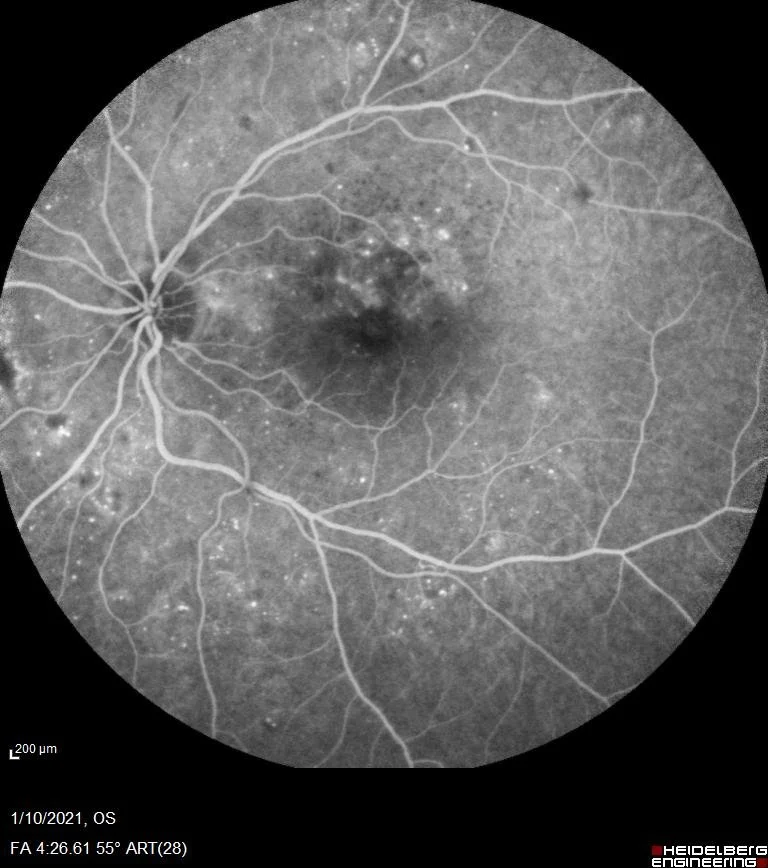

- Focal φωτοπηξία στις ισχαιμικές περιοχές, μετά από φλουοροαγγειογραφικό έλεγχο

- Panretinal φωτοπηξία (PRP) όταν υπάρχει παραγωγική αμφιβληστροειδοπάθεια

Τι περιλαμβάνει ο έλεγχος: Βυθοσκόπηση με μυδρίαση — OCT για ανίχνευση οιδήματος ωχράς — Σε ορισμένες περιπτώσεις: Angio-OCT ή φλουοροαγγειογραφία